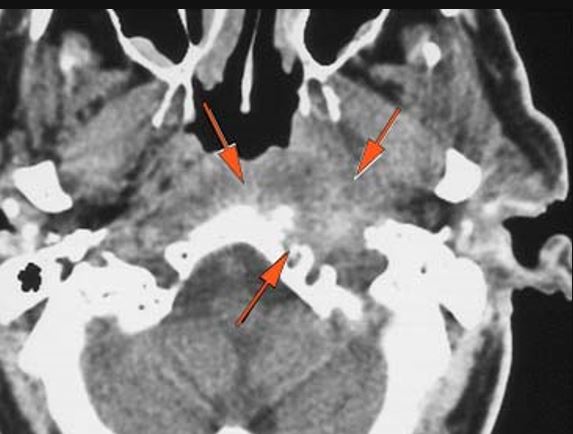

General Skull Base

There are localized, potentially subperiosteal, fluid or pus collection spreading along the petrous apex inferior surface (mainly below the carotid canal) and/or clivus. [Yes/No]

The basisphenoid and basiocciput (clivus) and/or the petrous apex inferior surface (mainly below the carotid canal) is eroded and/or its marrow space infiltrated. [Yes/No]

There is an erosive process, subperiosteal or otherwise spreading along the anterior-inferior aspect (extracranial aspect) of the petrous apex involving the bony Eustachian tube and/or carotid canal. [Yes/No]

The petrous apex is abnormal. [Yes/No]